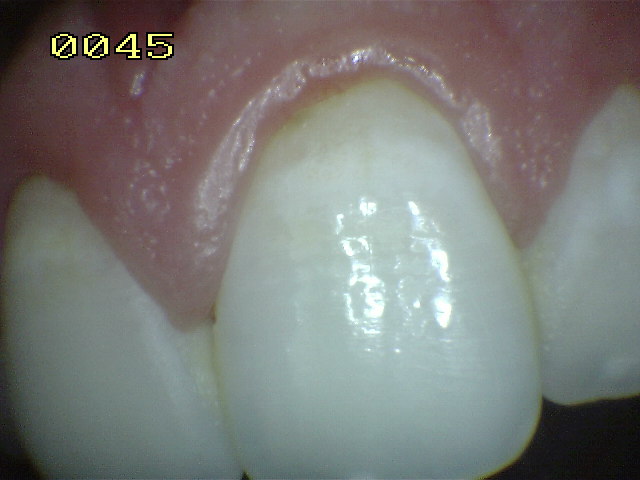

Grado 0 |